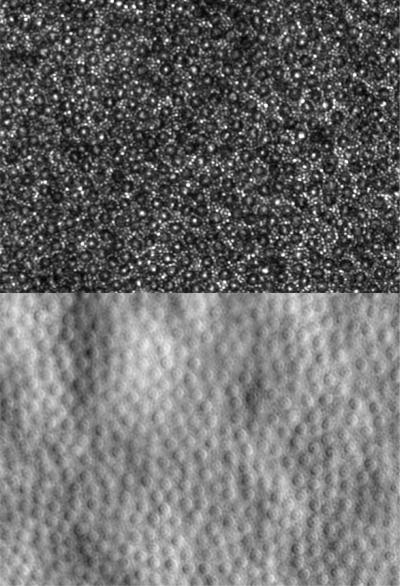

Cone photoreceptor cells in a living human eye

Cone photoreceptor cells imaged using annular pupil illumination combined with sub-Airy disk confocal pinhole detection. Confocal reflectance (top) and non-confocal split detection (bottom) images are simultaneously acquired in a living human eye.

Read the associated publication